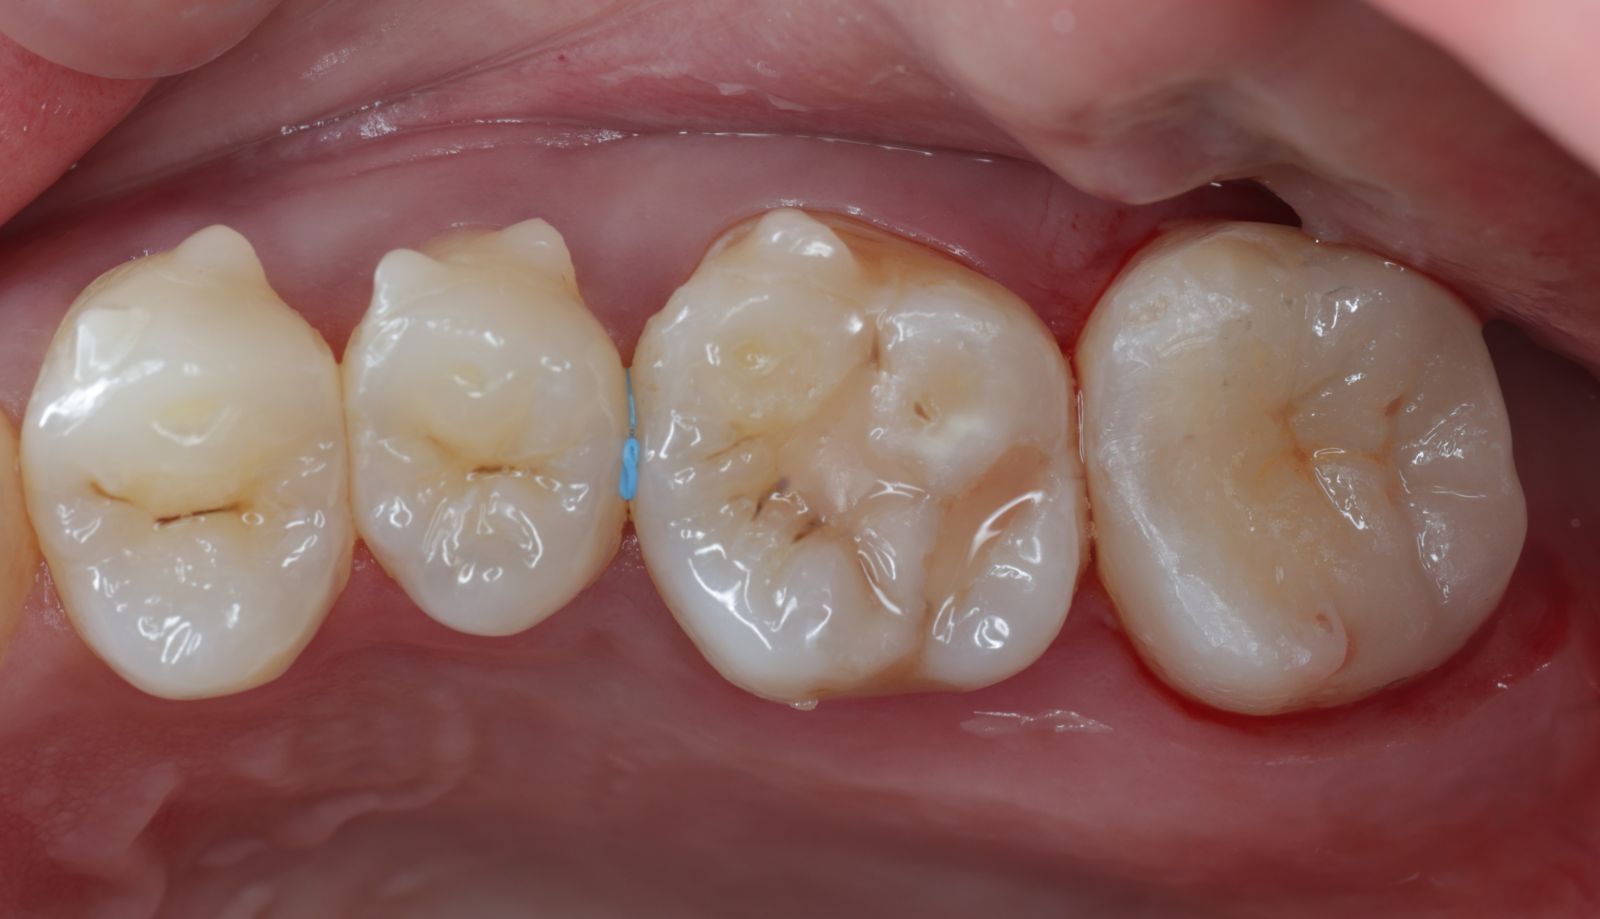

【 案 例 三】

- 有時候表面上看起來是蛀牙是一個小缺口,其實裡面已經是範圍很大的蛀牙了!用隔濕的小帳棚隔絕汙染、清理蛀牙,缺損的齒質就靠陶瓷齒雕(瓷塊)做修復!仿真的色澤及外觀,讓你看不出來牙齒曾經的損傷。